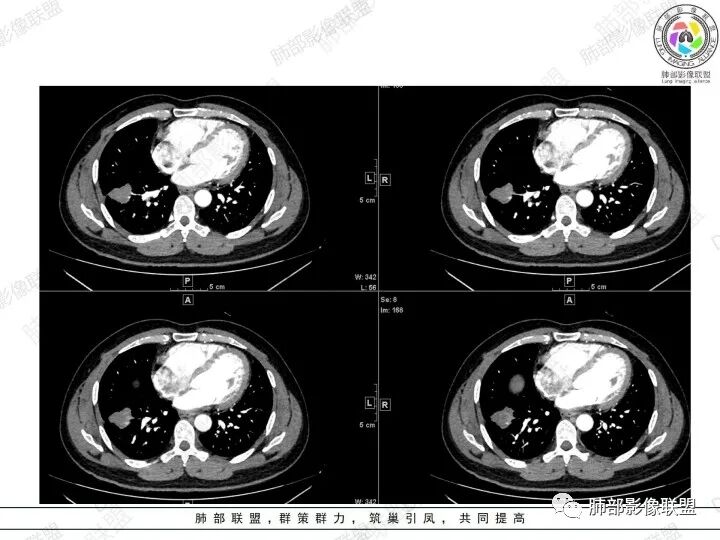

2、胸部CT右肺下叶胸膜下肿块性病变,边缘可见分叶毛刺、边缘膨隆,似有指状凸起,邻近胸膜稍牵拉凹陷,叶间裂以为不明显,提示收缩力较弱。近端支气管进入后截断,病灶内密度尚均匀,增强后可见轻度强化,未见空洞或钙化,并可见血管影进入。右侧肺门及纵隔内可见肿大淋巴结影。无胸腔积液。

3、综合患者临床症状及影像表现,需要考虑肿瘤性病变和非肿瘤性病变,肿瘤性病变需要考虑普通浸润性腺癌或结节型粘液腺癌、淋巴瘤、淋巴上皮瘤样癌、小细胞肺癌等,非肿瘤性病变主要考虑肺脑同病中的隐球菌。①普通浸润性腺癌,以肺外周多年、混合磨玻璃或实性结节/肿块,多见分叶、毛刺、胸膜凹陷、血管集束等征象,本例收缩力较弱、且强化偏轻,不够典型。②粘液腺癌,腺癌的特殊类型。多位于胸膜下(90%位于胸膜下,70%位于下叶胸膜下),边缘清或不清的GGO:提示粘液外渗,少数为纯GGO,缺乏中心纤维化区:毛刺、胸膜凹陷征少,很少胸膜侵犯,淋巴结转移少见,增强后无强化或低强化,本例病灶位于胸膜下,强化轻,收缩力弱,结节期粘液腺癌确实可以符合。③小细胞肺癌,吸烟男性多见,典型征象包括娘小崽大、腊肠样凸起、冰冻纵膈等,本例胸膜下病变大、但肺门淋巴结肿大程度较轻,不符合常见小细胞癌生物学行为,但有可疑指状凸起,小细胞肺癌不能完全除外。④淋巴上皮瘤样癌,少见的恶性肿瘤,患病年龄较轻,肿瘤多位于胸膜下,边缘多光滑,病灶周围可见磨玻璃,毛刺及分叶、胸膜凹陷少见,近端支气管可截断,增强多为中度-明显强化,本例除了强化程度偏轻外,影像表现基本可符合。⑤淋巴瘤,原发肺内淋巴瘤较少见,病灶多位于支气管血管束周围或胸膜下,密度多较均匀,边缘可膨隆也可平直收缩,可见支气管充气征、血管造影征等,强化多为轻中度,本例肺内结节血管穿行自然,局部有血管漂浮,长轴与支气管走行基本一致,肺门淋巴结肿大,不能排除。⑥隐球菌,影像表现可分为孤立结节型、大片实变型、多发结节或实变型、弥漫型。病变多位于胸膜下,边缘平直为主、可伴晕征,可见支气管穿行、部分可见支气管截断,密度多较均匀,部分可伴空洞,增强多为轻中度强化、延迟强化。本例病变位于胸膜下,收缩力弱,强化程度轻,但没有呼吸道症状,病变近端支气管截断,肺门淋巴结大,这些征象都难以用隐球菌解释,基本排除。

总之,本例考虑到恶性肿瘤性病变多不困难,但诊断到粘液性癌并不容易。